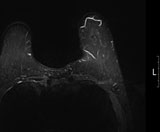

유방 MRI

The center utilizes advanced techniques for breast cancer diagnosis, such as fine-needle aspiration cytology, stereotactic biopsy, and Mammotome biopsy, which enhance both diagnostic accuracy and the success rate of tumor excision. Once breast cancer is confirmed, various tests are performed to determine the cancer stage. Using PET, MRI, whole-body bone scans, and chest/abdominal CT scans, the center accurately evaluates metastasis and determines the patient’s preoperative cancer stage.